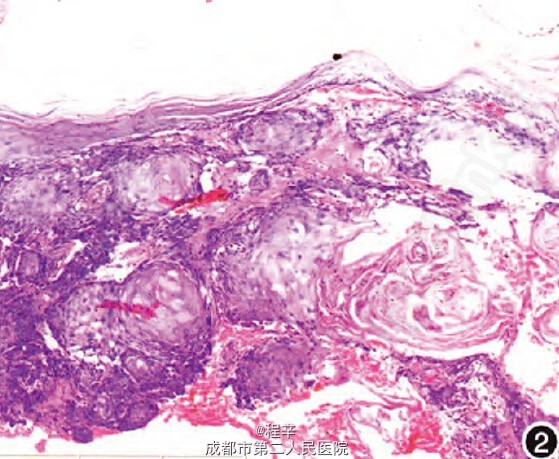

诊断:慢性放射性皮炎继发鳞状细胞癌。 治疗:给予阿维A 10 mg,每天2次口服,局部对症予以莫匹罗星软膏、复方泼尼松软膏、尿囊素外用。嘱患者注意手部保暖及避免外伤、感染。治疗2个月后随访,右手肿胀基本消退,溃疡基底清洁,愈合尚可,手部其他部位皮损明显改善,治疗期间检测肝肾功能及血脂均在正常范围。目前,患者仍继续口服阿维A 20 mg/d,双手掌角化脱屑继续好转,原有皮损无发展,亦无新发皮损出现,但原溃疡处难以愈合,请本院外科会诊,建议择期手术切除病变处并予以植皮。